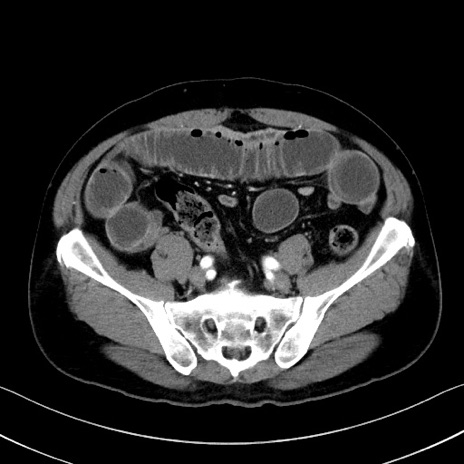

症例35(横断像)

【症例】70歳代 男性

【主訴】腹部膨満、嘔吐

【現病歴】昨日より腹部膨満感出現。本日増悪し、仙痛出現。嘔吐あり、受診。

【既往歴】糖尿病、胆摘後

【身体所見】BP 149/80mmHg、HR 74/min、BT 35.9℃、腹部:膨満、軟、圧痛なし。腸雑音減弱あり。上腹部正中切開瘢痕あり。

【データ】WBC 13500、CRP 1.72